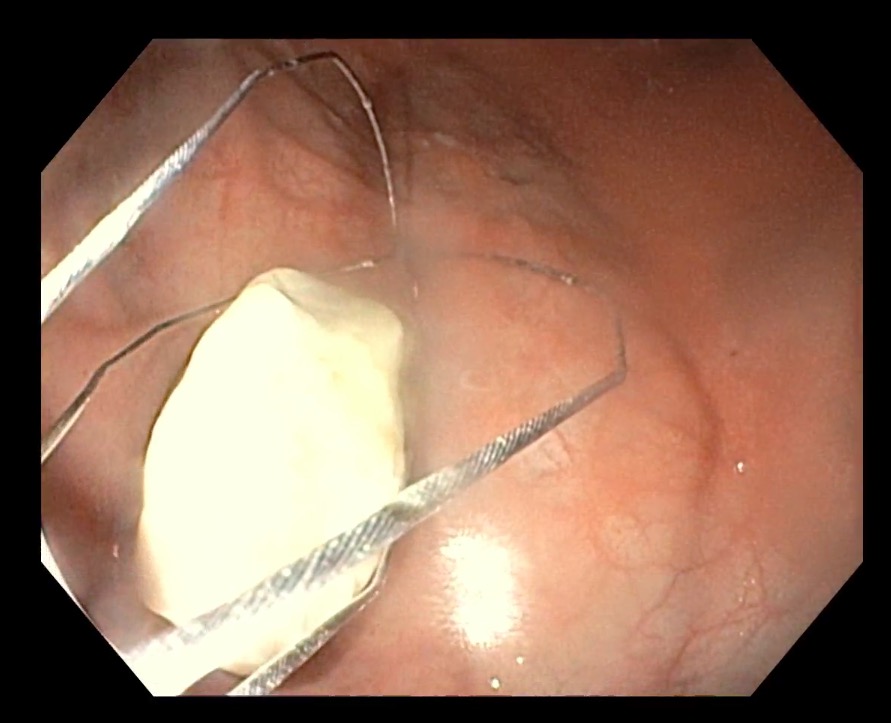

体格や腸の径に対して異物のサイズが大きかったため、飼主様と相談の上、麻酔下内視鏡により異物を取り出す処置を行うこととなりました。

内視鏡の映像。バスケット型の先端を広げたり閉じたり出来るため、石を掴むことができます。